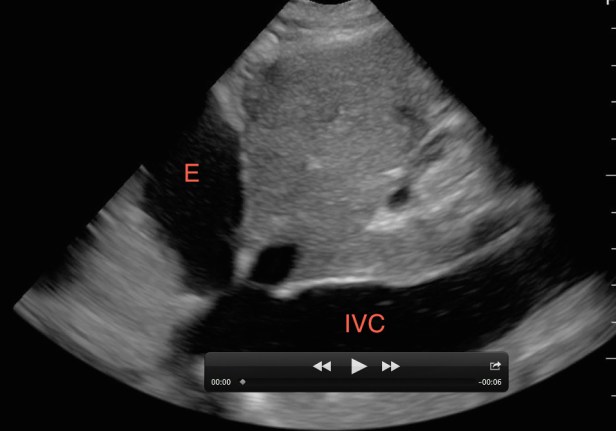

While viewing the heart in the sub-xiphoid window, point the probe’s indicator toward the patient’s head and reduce the angle of the transducer to evaluate the inferior vena cava (IVC). A pericardial effusion with a non-distensible IVC is very worrisome for tamponade. If there is respiratory variability, tamponade is excluded with few exceptions. Without a pericardial effusion, a non-distensible IVC is consistent with fluid overload states. An IVC that varies in diameter widely during respirations suggests an etiology other than heart failure.[12]

Figure 2. A non-distensible (plethoric) IVC with a pericardial effusion (E) consistent with tamponade physiology.